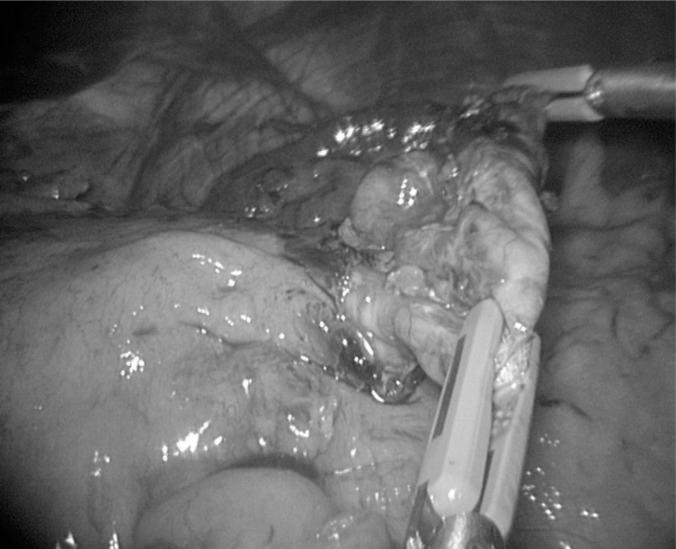

The patient is a 45-y-old male presenting with a 4-mo case of dysphagia, small amounts of regurgitation, and abdominal pain but no other symptoms.

RESULTS

The patient was diagnosed with a gastric diverticulum, which was subsequently successfully treated with a laparoscopic gastric diverticulectomy.

该患者被诊断为胃憩室,随后通过腹腔镜胃憩室切除术成功治愈。